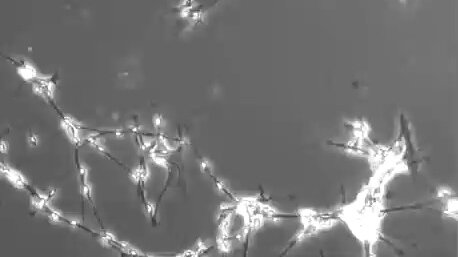

Образование нейронных связей.